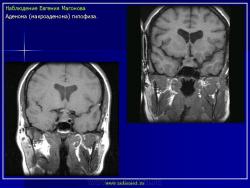

ГМ. Патология области турецкого седла. Набор изображений. +

Патология области турецкого седла.

впервые настолько глубокие изменеия турецкого седла, что даже не требуется дообследование.